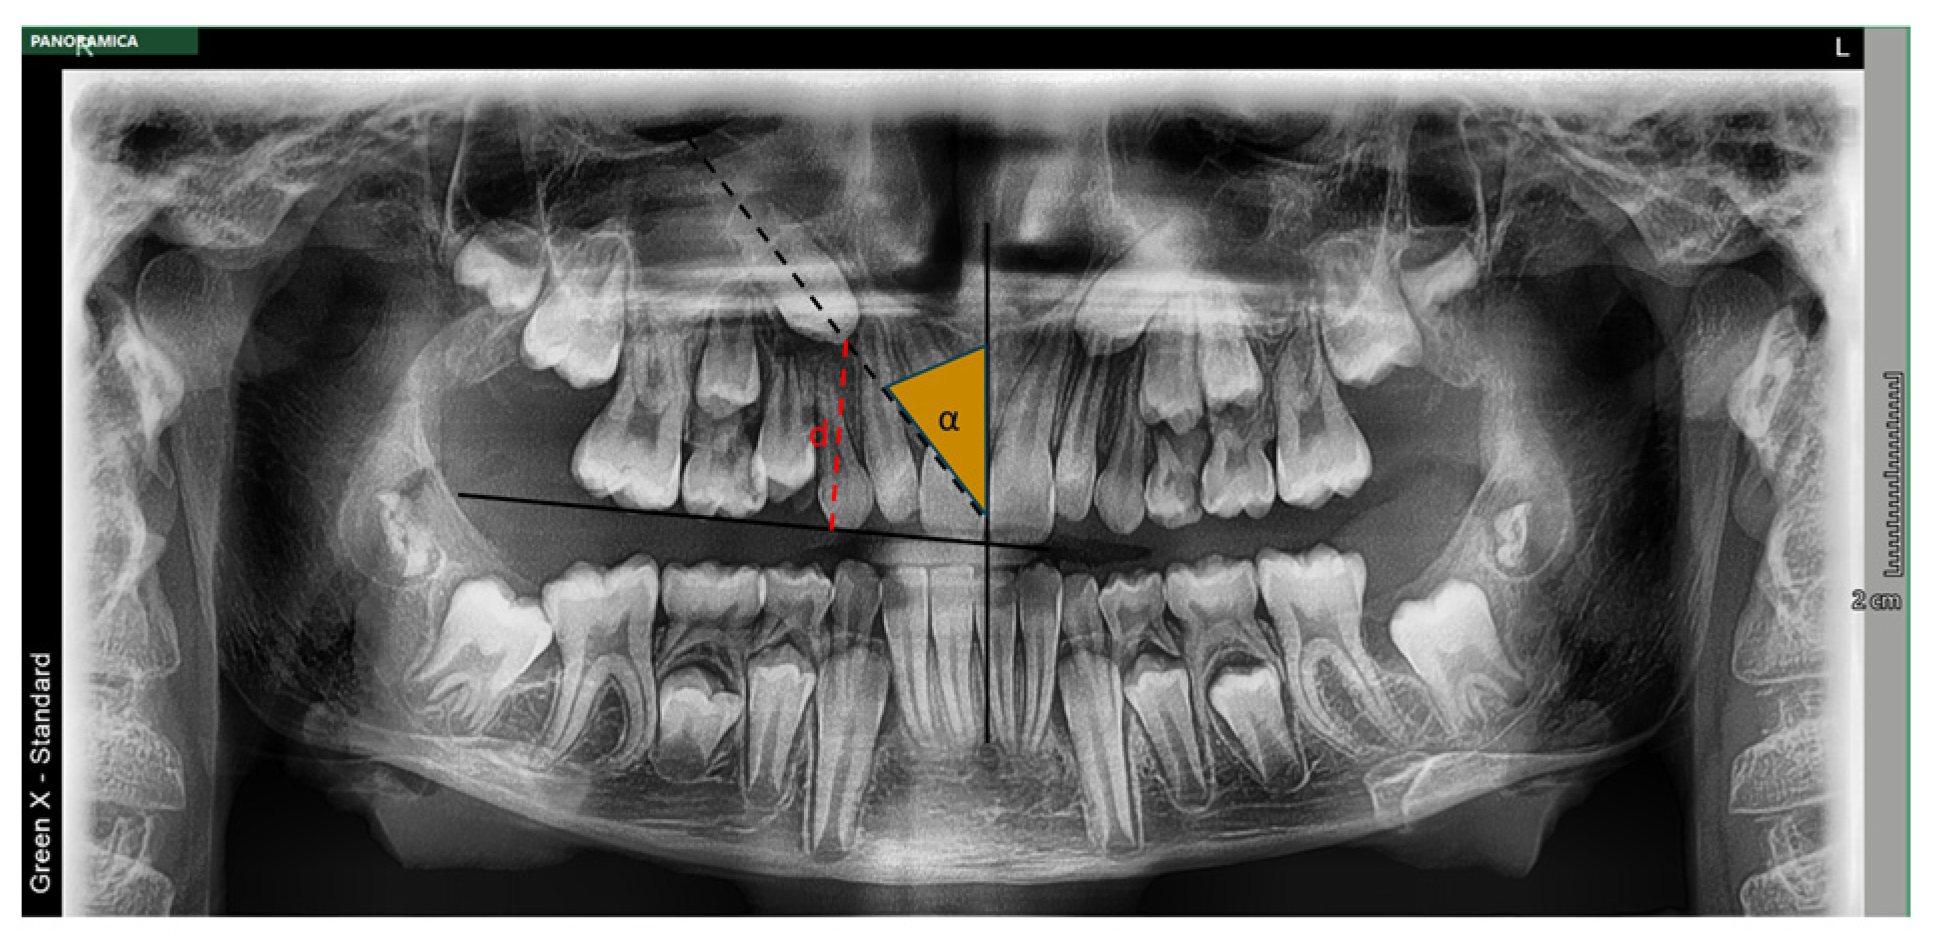

- Distance d from the occlusal plane (mm): This was defined as the perpendicular distance from the impacted canine’s cusp tip to the occlusal plane [46].

- Angle α (degrees): This indicates the mesial inclination of the crown to the midline and is measured as the angle between the interincisal midline and the long axis of the impacted canine. Angular measurements between 0 and 25° were classified at low-moderate risk of inclusion, while measures ≥ 25° were classified at high-risk of inclusion [39].